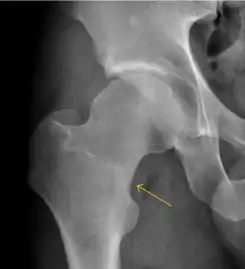

Slipped capital femoral epiphyses (SCFE) usually affect 11- to 14-year-old adolescents (Figure 4). Radiographs may show widening and irregularity of the physis and posterior inferior displacement of the capital femoral epiphysis. On the AP view Klein’s line, tangent to the lateral aspect of the femoral neck, does not intersect the femoral head indicating that it is displaced. SCFE may compromise the blood supply to the femoral head and cause avascular necrosis, mainly when there is instability between the fragments.[1]

Figure 4: (a) X-ray of a 10-year-old child with left hip pain. It was considered normal at emergency despite the widening of the left physis (arrow). Two weeks later epiphysiolysis was evident (b). Despite appropriate surgical reduction (c) osteonecrosis developed and femoral head collapsed 1 month later (d).[1]